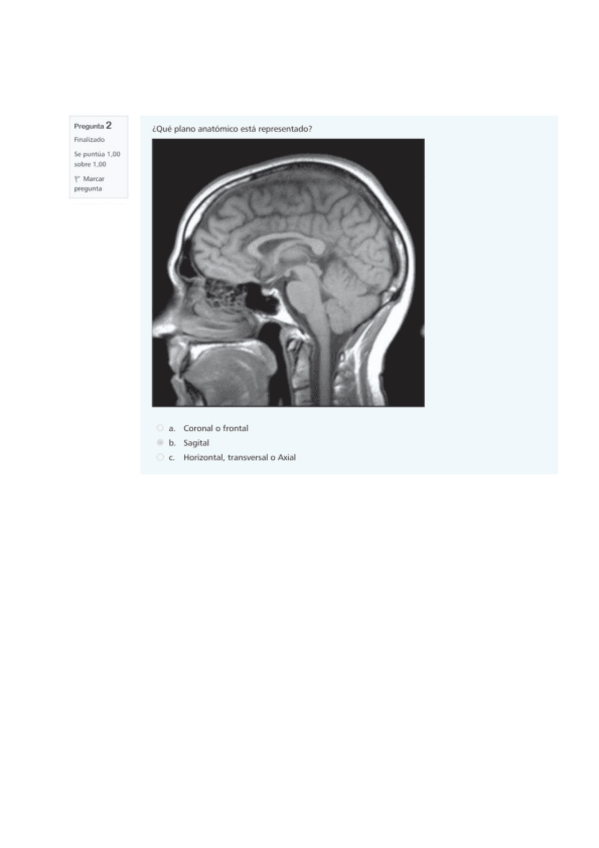

He publicado nuevos examenes de 1º Anatomía Humana: tipotestresuelto.pdf

33 páginas